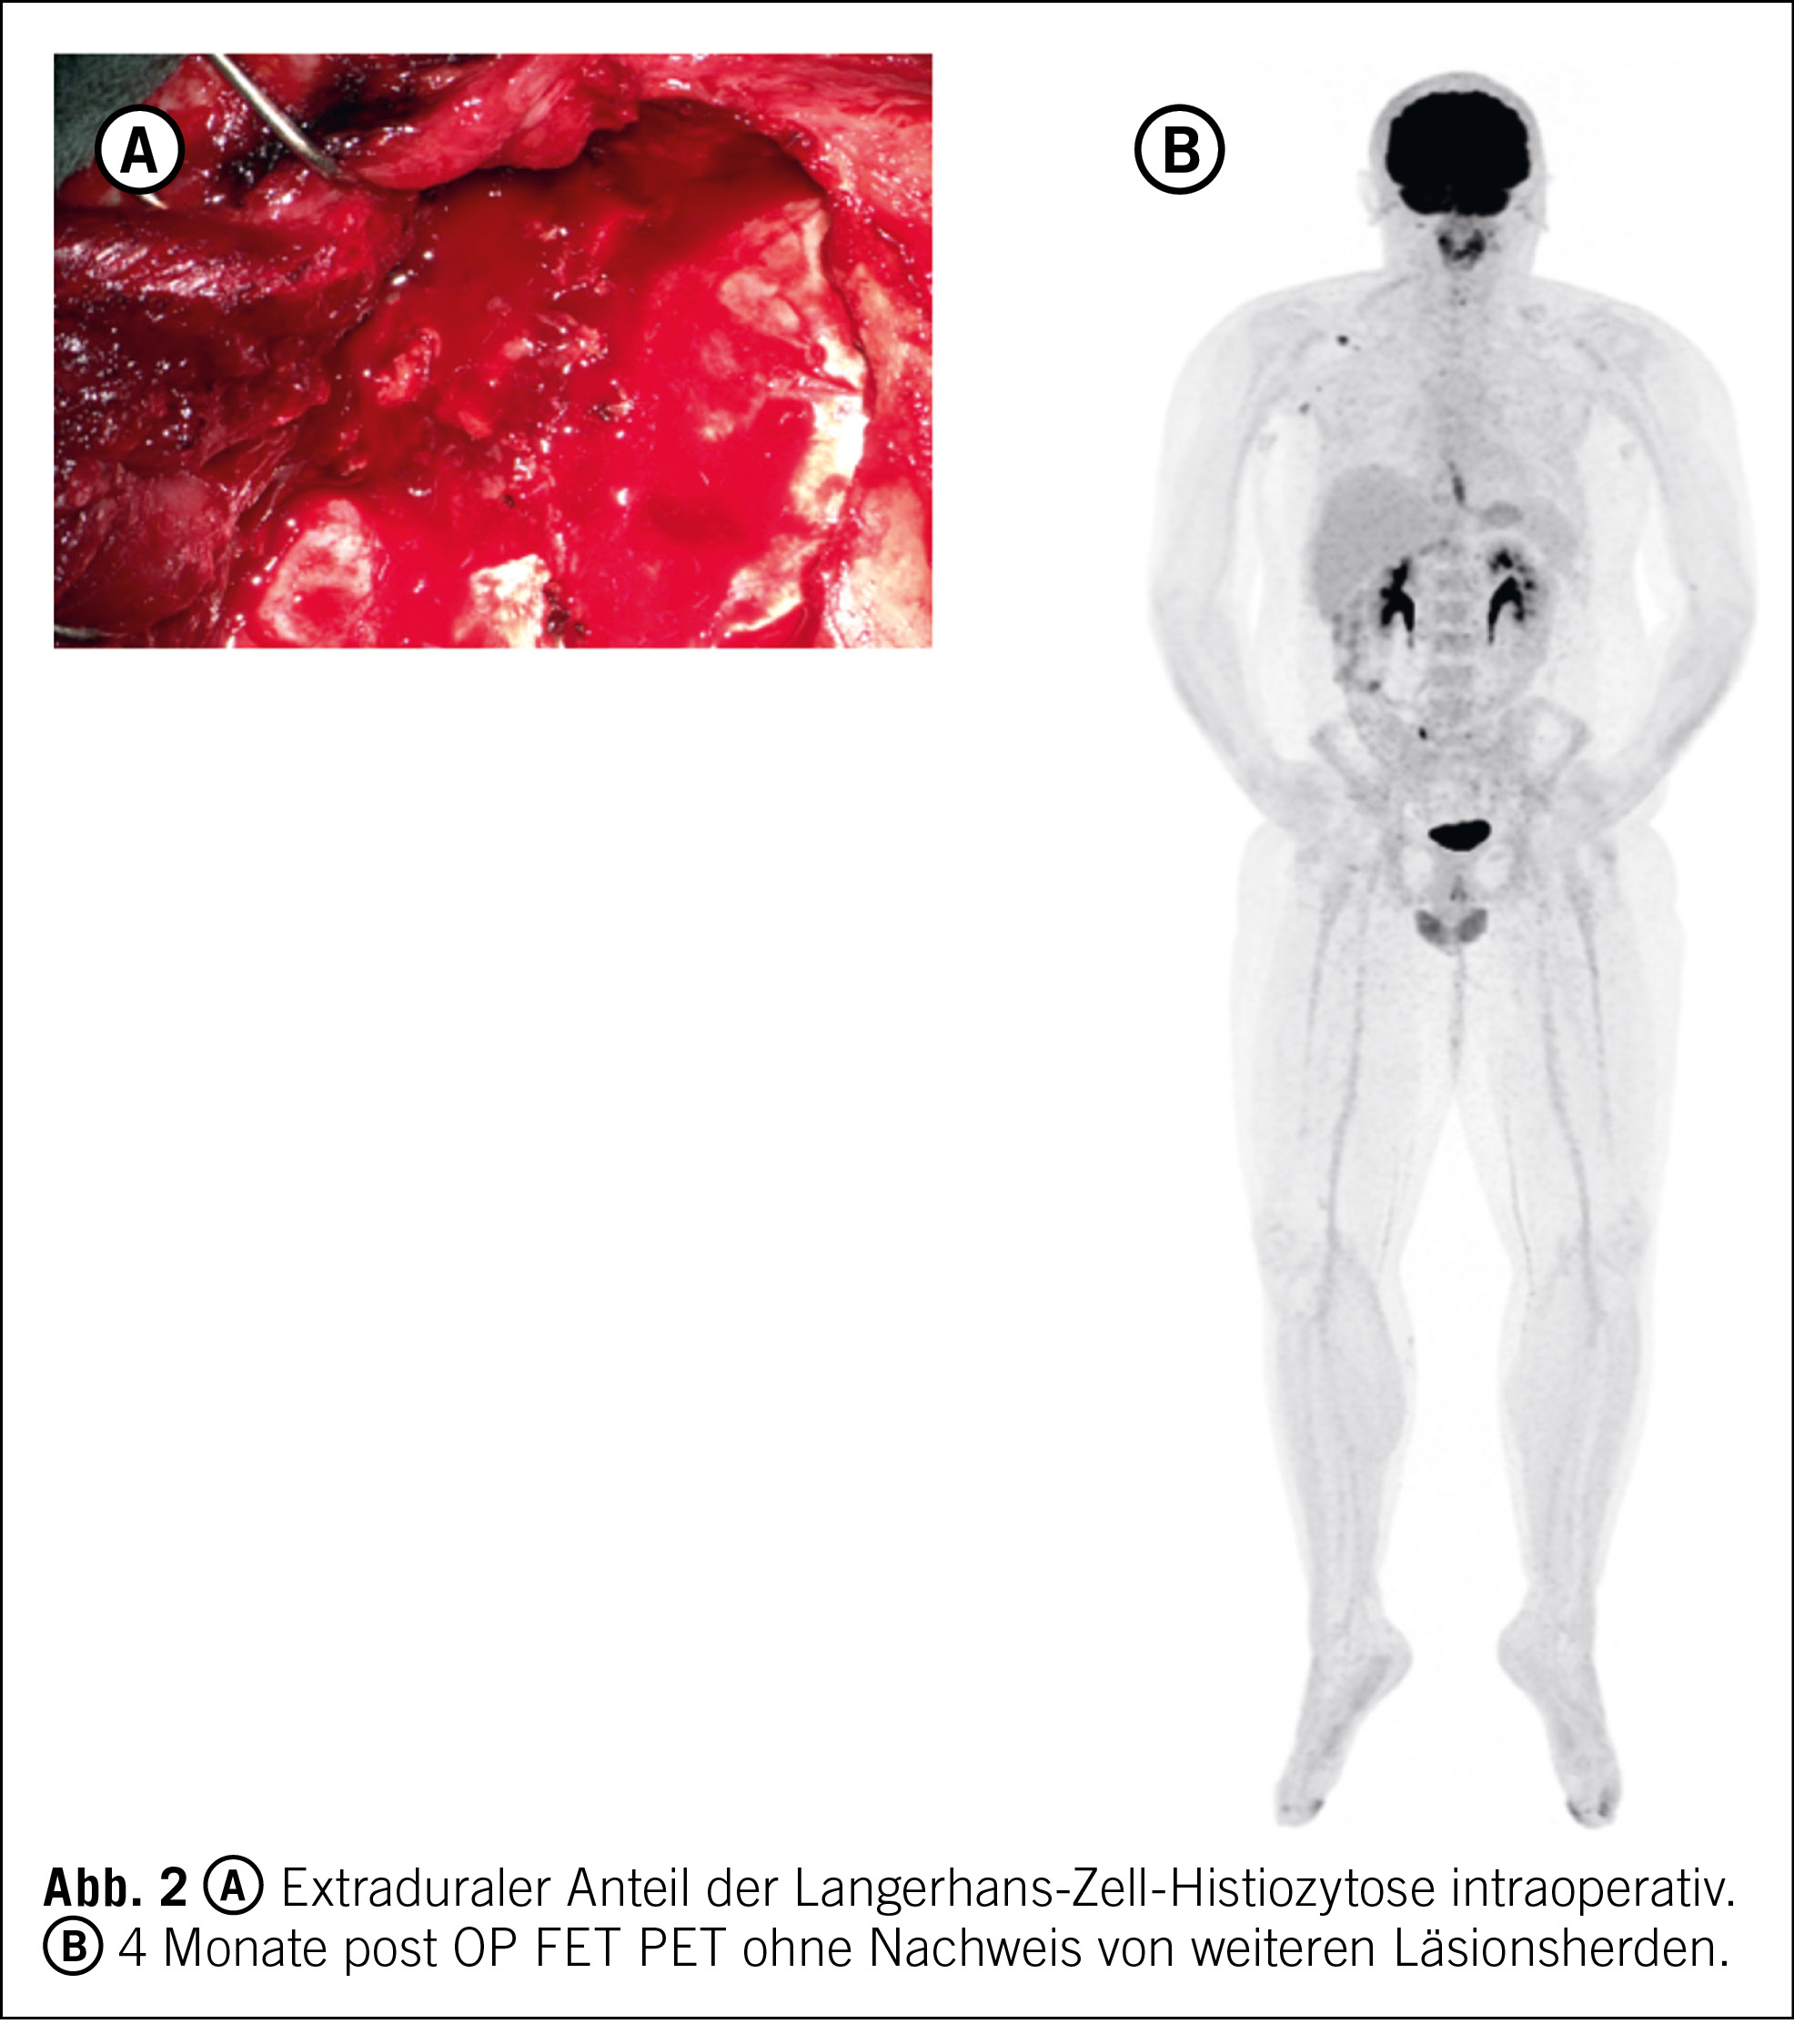

Es findet sich eine 14 x 11 x 11 mm grosse Osteolyse des Os temporale links ohne Randsklerose und ohne Orbitabeteiligung. Fokal randständig grenzt eine kontrastmittelaufnehmende Weichteilläsion von ca. 2 cm Durchmesser mit bikonvexer Vorwölbung der Weichteile an. Nach i. v.-Kontrastmittelgabe sonst kein pathologisches intraaxiales Enhancement des Hirnparenchyms. Keine intrakranielle Blutung. Normal kontrastierte intrakranielle grosse venöse Blutleiter (Abb. 1 A).

Es zeigt sich eine kragenknopfartige Weichteilformation links-temporal mit Destruktion der lokoregionären Schädelkalotte, die breitbasig den meningealen Strukturen aufsitzt, eine zentrale Nekrose aufweist und den linken M. temporalis diffus infiltriert. Als mögliche bildmorphologische Differenzialdiagnosen werden ein Hämangioperizytom, ein hochgradiges Meningeom, eine Solitärmetastase bei unklarem Primarius oder ein eosinophiles Granulom diskutiert. Die übrige Schädelkalotte, Weichteile, zerebrale sowie intrakranielle Strukturen sind ohne pathologischen Befund (Abb. 1 B und C).

Zur Diagnosesicherung ist eine histologische Aufarbeitung unumgänglich. Aufgrund des umschriebenen und chirurgisch gut zugänglichen Befundes wird der Entscheid zur mikrochirurgischen Komplettresektion der Läsion mit Rekonstruktion der Schädelkalotte gestellt. Der Eingriff kann komplikationslos durchgeführt und das Resektat der neuropathologischen Aufarbeitung zugeführt werden (Abb. 2 A).

Es zeigt sich ein perioperativer komplikationsloser Verlauf ohne fokal-neurologische Defizite. In der postoperativen MRI zeigt sich eine Komplettresektion, und der Patient ist beschwerdefrei (Abb. 1 D und E). Eine vier Monate nach der Operation durchgeführte F-18-Fluorethyltyrosin, Radionuklid (FET) Positronen-Emissions-Tomographie (PET) CT gibt keine Hinweise auf weitere Läsionen (Abb. 2 B)